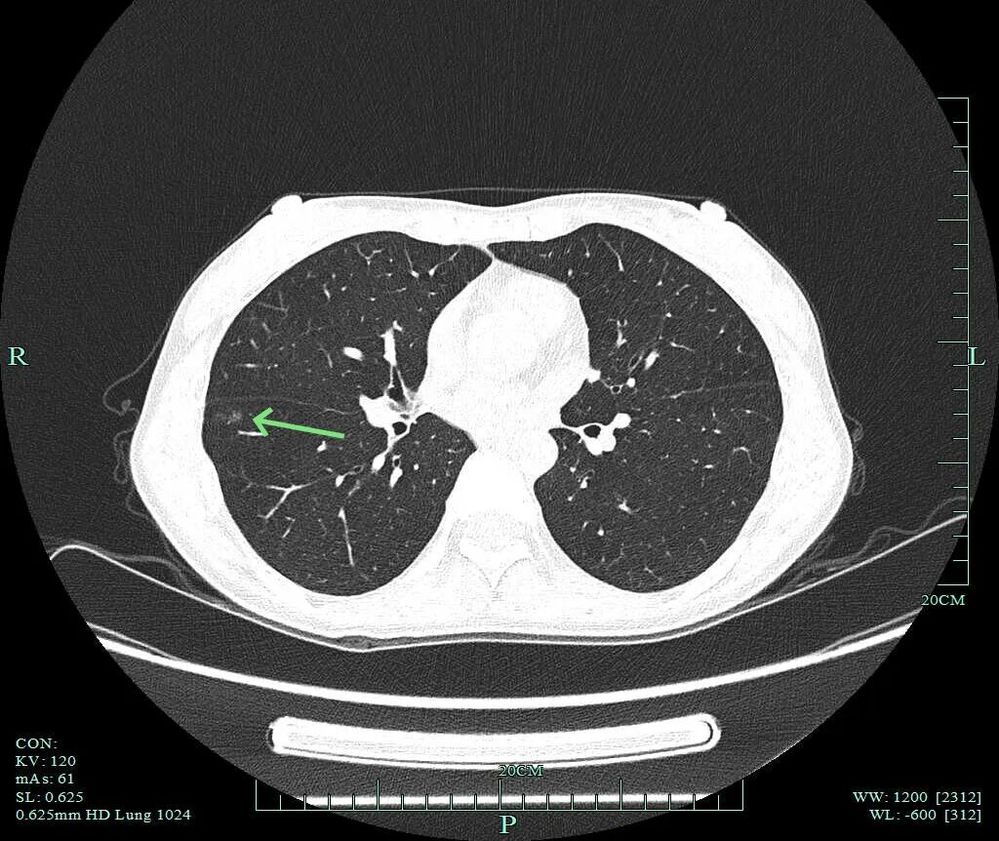

灶内密度不均,叶间裂处增厚与密度增高,血管进入,表面不平以及细毛刺可见。

病灶混合密度,实性成分有收缩力与纠集感,磨玻璃部分密度较低,表面不平,细毛刺可见,紧贴叶间裂。